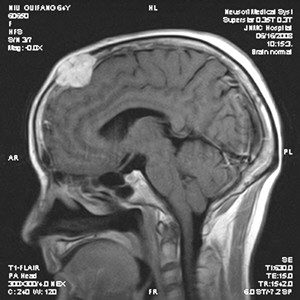

顱骨骨瘤是一種生長緩慢的良性骨腫瘤,與周圍顱骨分界常不清楚,可以發(fā)生于顱骨的任何部位。常見單發(fā),但亦有多發(fā)或聚發(fā)于一處者。青中年好發(fā)。瘤體較小者一般無自覺癥狀,較大者局部輕微脹痛或麻木感,體檢局限腫塊,基底寬,表面光滑與頭皮無粘連,無壓痛。位于顱底或鼻竇處,出現(xiàn)腦神經(jīng)受累癥狀及鼻塞。生長緩慢無癥狀的小骨瘤,可予觀察處理;生長較快,瘤體大及有腦受壓癥狀者,手術(shù)治療。腫瘤切除后顱骨缺損范圍大者同期行修補(bǔ)術(shù)。無特效藥物治療,手術(shù)者,術(shù)后使用抗生素治療一周左右。

顱骨骨瘤是一種常見的良性腫瘤,特點(diǎn)是生長緩慢、不痛、廣基,與周圍顱骨分界常不清楚。可以發(fā)生于顱骨的任何部位,以額骨和頂骨...【詳細(xì)】

顱骨骨瘤是一種常見的腫瘤,許多骨瘤較小,又沒有明顯的癥狀,易于忽略,故很難有確切的發(fā)病率。顱骨骨瘤多生長在額骨和頂骨,其...【詳細(xì)】

顱骨骨瘤是一種常見的良性腫瘤,特點(diǎn)是生長緩慢、無痛、廣基,與周圍顱骨分界常不清楚?梢园l(fā)生于顱骨的任何部位,以額骨和頂骨...【詳細(xì)】